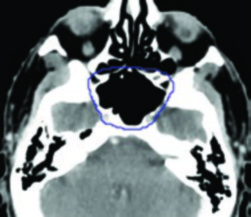

O capítulo de nasofaringe abre a série com um foco direto em princípios gerais de planejamento e delineamento. Isso já define o tom do livro: antes de discutir casos específicos, o alvo precisa ser entendido com método. Para seguir esse raciocínio em detalhe, revise o artigo dedicado ao carcinoma de nasofaringe.

Nos tumores sinonasais, o livro insiste que não existe um único comportamento biológico. A página de abertura já lista histologias muito diferentes, como carcinoma escamoso, adenocarcinoma de glândulas salivares menores, carcinoma adenoide cístico, estesioneuroblastoma e carcinoma sinonasal indiferenciado. Como cavidade nasal e seios se comunicam por múltiplos óstios e septos finos, a extensão local para cavidades adjacentes vira parte central do planejamento. Para ver o capítulo inteiro, acesse o artigo dedicado a cavidade nasal e seios paranasais.